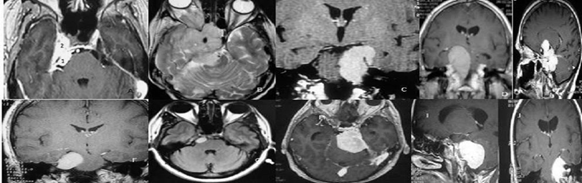

Figura 2: El estudio de la posición del tumor en el clivus, y la extensión o no de éste en la fosa media, sirve para decidir el abordaje. Para los tumores con un componente solo en el clivus superior, se utilizó un abordaje pterional pretemporal, abriendo la muesca de la carpa y eliminando el tumor del clivus superior que estaba comprimiendo el nervio trigémino y causando neuropatía (A). Para este meningioma esfenopetroclvial anaplásico se utilizó el abordaje craneo-órbito-cigomático con petrosectomía anterior con extirpación tumoral. El paciente se sometió previamente a cirugía con ojo congelado (frozen eye) (B). El abordaje petroso posterior (pre-sigmoide supra / infratentorial) se usa para meningiomas petroclivales con extensión tumoral en la fosa media (C, D, E). Para los meningiomas petroclivales localizados completamente en la fosa posterior, el abordaje retrosigmoideo es suficiente independientemente del tamaño del tumor (F, G, H, I, J).